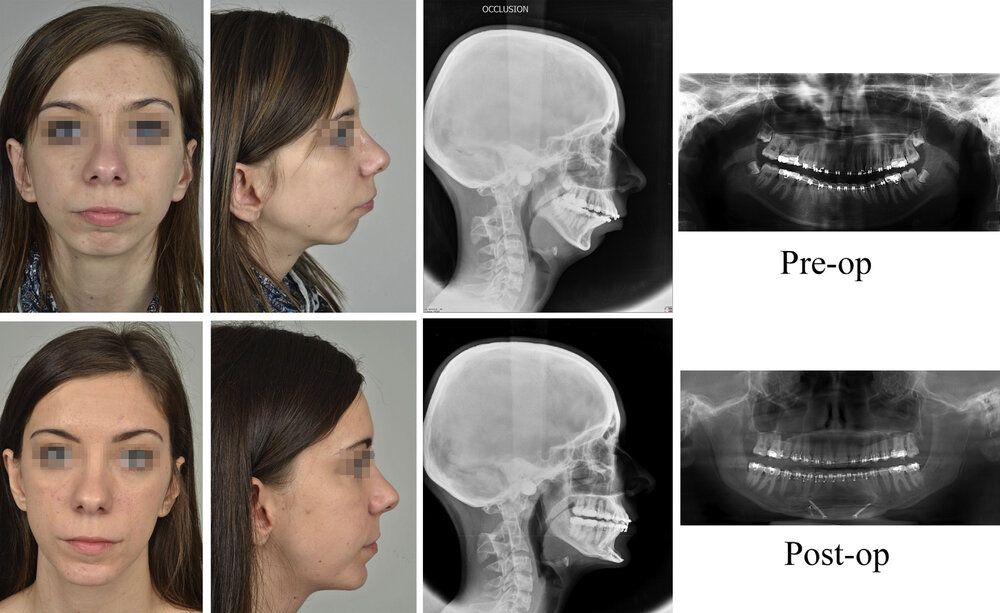

Fig.4. Case 1. Treatment outcomes at 6 months postoperatively. Frontal and profile photographs, profile X-ray and orthopantomogram in preoperative time (top) and at 6 month (bottom).